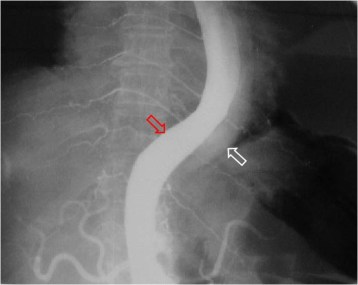

SIGNO DE LA DOBLE LUZ AÓRTICA

Imagen de aortografía en un paciente con disección. La luz verdadera está marcada con la flecha roja y la falsa con la blanca. Puede verse un ejemplo del signo en la resonancia en el Signo del colgajo (o flap) intimal.